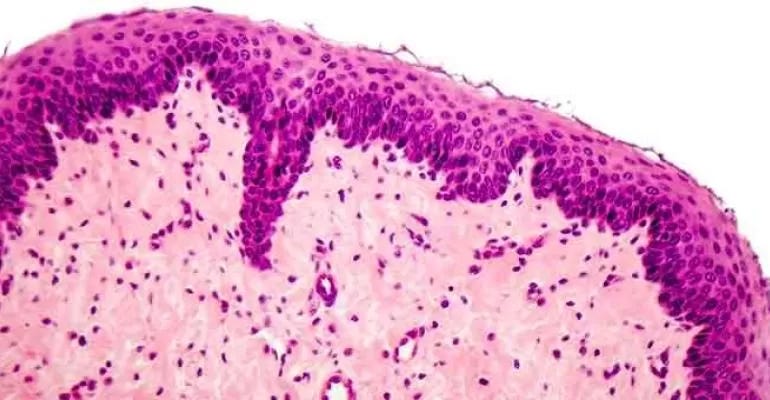

The teaching, learning and practice of pathology depends on good understanding of microscopic morphology. Demonstrating microscopic features and understanding those by conventional method is often frustrating. Practicing pathologists also need affordable hardware and software to capture, share, preserve and print histopathology images. Camera attachment, multi head microscope, digital microscope and virtual microscopy are available but these are expensive, take table space, and only few institutes/ pathologists with limited resources can afford to invest in these.

Rise of digital cameras have generated a shift toward digital-image capturing methods, including mounted digital cameras and whole slide digital-slide scanning. Digital image capture techniques – whole slide imaging (WSI) have introduced new applications for slide sharing and second-opinion consultations of unusual or difficult cases in pathology. This has created a new branch: digital pathology. Digital pathology is an image-based information environment which is enabled by computer technology that allows for the management of information generated from a digital slide. Digital pathology is enabled in part by virtual microscopy, which is the practice of converting glass slides into digital slides that can be viewed, managed, and analysed on a computer monitor. With the advent of Whole-Slide Imaging, the field of digital pathology has exploded and is currently regarded as one of the most promising avenues of diagnostic medicine in order to achieve even better, faster and cheaper diagnosis, prognosis and prediction of cancer and other important diseases. Updates on digital pathology can be found on Digital Pathology Association website.

With their recent surge in popularity, smart phone cameras have become a widespread cost-effective method for pathology image acquisition. In addition, software/apps/technologies useful for image and video management are freely available from Google app store. Therefore, we thought of exploring the possibility of smartphones and its technologies as an affordable way to get introduced to basic functions/ applications of digital pathology.